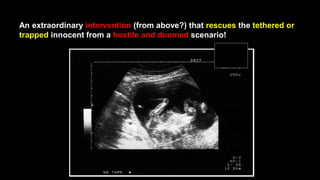

An extraordinary intervention (from above?) that rescues the tethered or

trapped innocent from a hostile and doomed scenario!